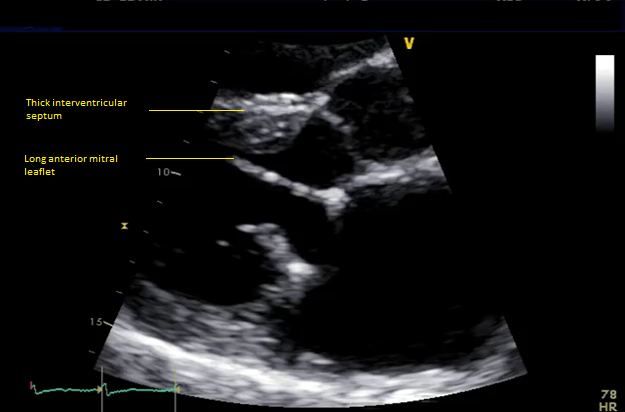

Six months later, the patient had continued shortness of breath and a transesophageal echocardiogram revealed severe mitral regurgitation with evidence of mild peri-prosthesis leak (video 2). Due to his elevated surgical risk (STS score of 9%),patient underwent a valve-in-ring (ViR) transcatheter mitral valve replacement (TMVR) with a 29mm Edwards Sapien3 via a trans-septal approach (using 14mm balloon for septostomy). Pre-procedure planning was done based on transthoracic & transesophageal echocardiography and multi-detector CT (without measurement of neo-LVOT with a simulated valve) showing long anterior leaflet (27mm), thick interventricular septum (1.5cm), LVOT diameter (1.8cm), aorto-mitral angle of 64 degrees (Figure 1, video 1). Immediately post TMVR, patient did well with stable hemodynamic but over next 2-3 days systemic pressures started to drop along with decline in renal function was noted. Trans-thoracic echocardiogram showed systolic anterior motion (SAM) of the anterior mitral leaflet with elevated LVOT gradient of 88mmHg (baseline LVOT gradient of zero mmHg prior to TMVR). Furthermore, there was evidence of a continued iatrogenic atrial septal defect with continuous left to right shunt. Percutaneous left ventricular assist device (Impella CP) was placed for hemodynamic support for 24 hours with improvement in renal function. The patient underwent alcohol septal ablation of 1st large septal perforator (injected 1.5ml of pure alcohol) with drop of LVOT gradient from 80 mmHg to 20mmHg. Next further septal ablation was performed by injecting another 1 ml of pure alcohol into the basilar branch of 2nd septal perforator with final LVOT gradient of 10mmHg (video 3).The patient was able to be discharged and his renal function recovered, however, he still continued to have NYHA functional class III symptoms.

Figure 1 Pre-mitral valve replacement multi-detector CT scan showing thick interventricular septum and aorto-mitral angle (panel A), and transesophageal echocardiogram showing long anterior mitral leaflet and left ventricular outflow tract diameter.

Video 1 Transthoracic echocardiogram at baseline showing long anterior mitral leaflet and moderately thickened interventricular septum.